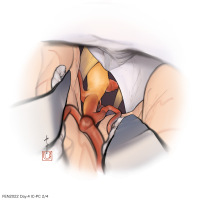

FEN2022シリーズ